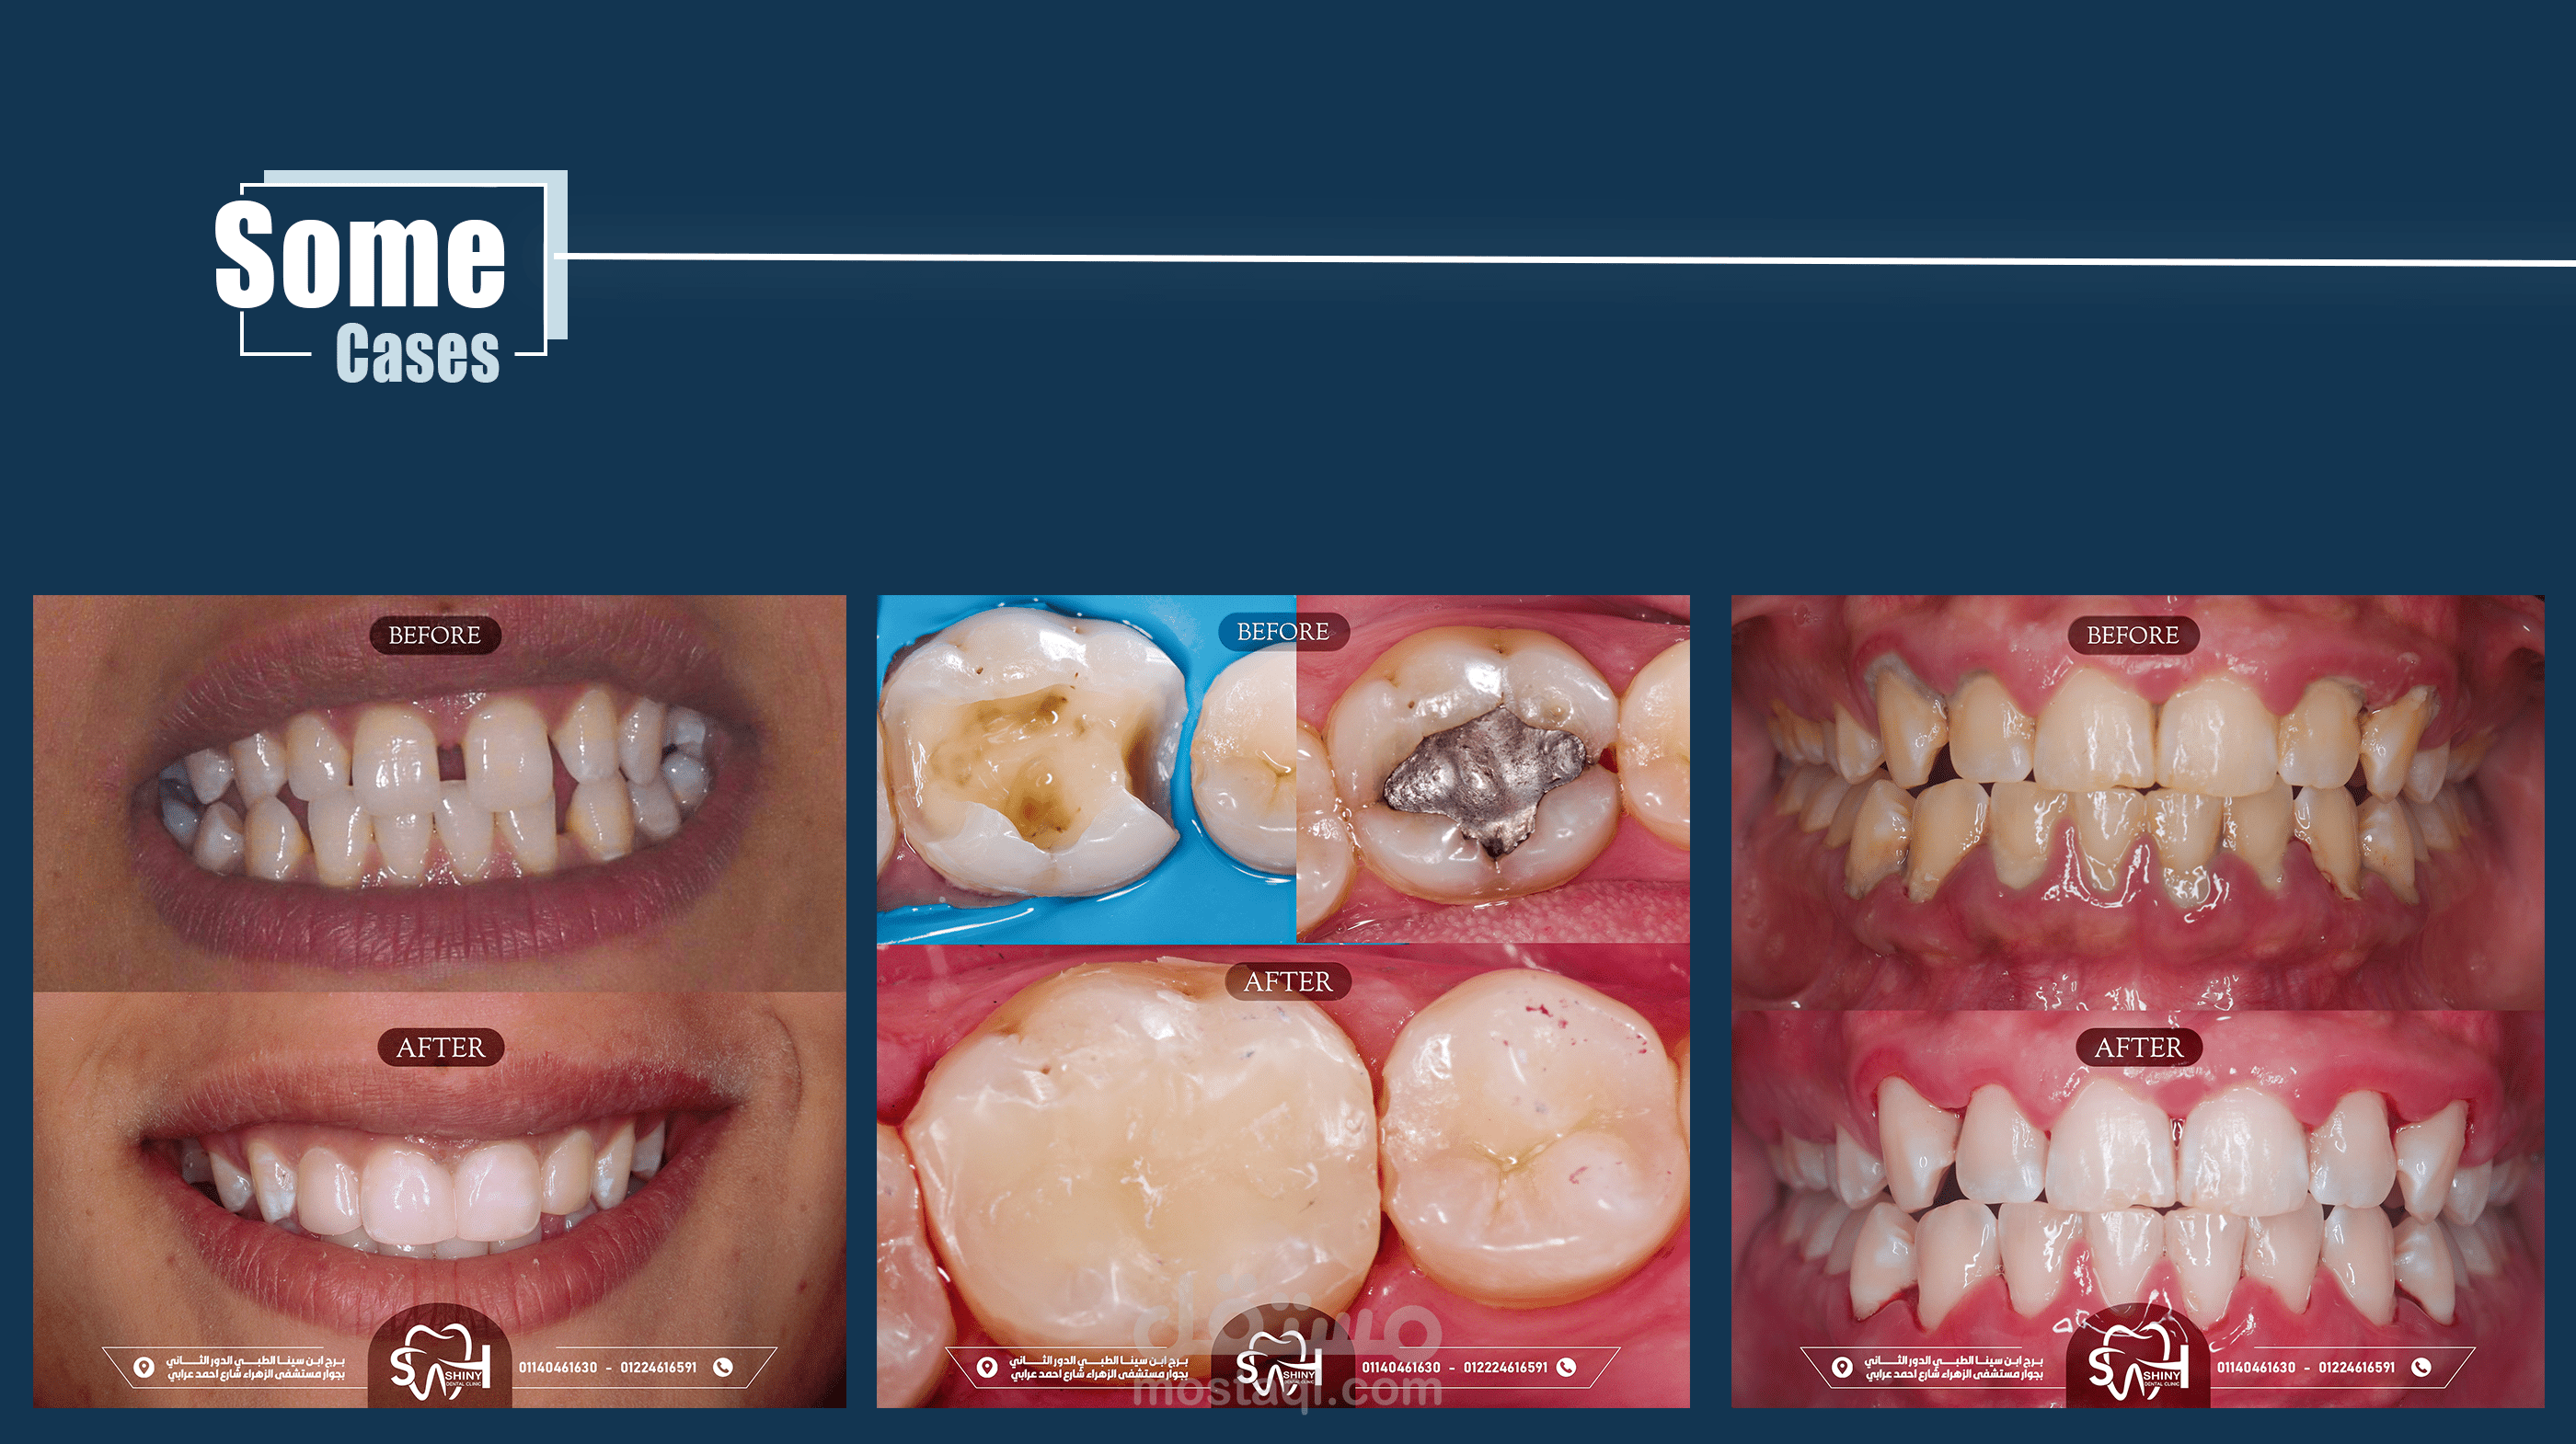

تصاميم سوشيال ميديا لصالح عيادة اسنان- shiny dental clinic.

هذه المجموعة من التصاميم تم إعدادها خصيصًا لعيادة shiny dental clinic, ,وهي تهدف إلى تعزيز الهوية البصرية للعيادة على منصات التواصل الاجتماعي، وزيادة التفاعل مع الجمهور, مع تسليط الضوء على الخدمات المقدمة والعروض الخاصة. تم التركيز في التصاميم على الألوان النظيفة والمريحة التي تعكس طابع العيادة الحديث والاحترافي، مع الحفاظ على أسلوب بسيط وجذاب يواكب تطلعات الجمهور المستهدف.